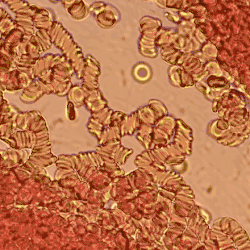

Rouleaux (sing. rouleau) are stacks or aggregations of red blood cells (RBCs) that form due to the unique discoid shape of the cells in vertebrates. The flat surface of the discoid RBCs gives them a large surface area to make contact with and stick to each other; thus forming a rouleau. They occur when the plasma protein concentration is high, and, because of them, the ESR (erythrocyte sedimentation rate) is also increased. This is a nonspecific indicator of the presence of disease.[1]

Conditions that cause rouleaux formation include infections, multiple myeloma, Waldenström's macroglobulinemia, inflammatory and connective tissue disorders, and cancers. It also occurs in diabetes mellitus and is one of the causative factors for microvascular occlusion in diabetic retinopathy.

So, the presence of rouleaux can also be a cause of disease because it will restrict the flow of blood throughout the body because capillaries can only accept free-flowing singular and independent red blood cells.